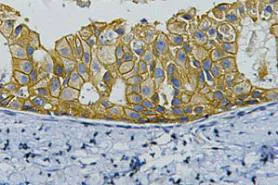

CDX2(14H6)Mouse Monoclonal Antibody

Cat: AMM08595

Size1:50μL Price1:$118

Size2:100μL Price2:$220

Size3:200μL Price3:$380

Application:WB,IF-P,IF-F,ICC/IF,IHC-P

Reactivity:Human,Mouse,Rat

Conjugate:Unconjugated

Optional conjugates: Biotin, FITC (free of charge). See other 26 conjugates.

Gene Name:CDX2